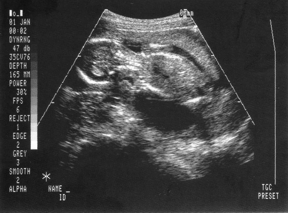

Hasi uh...Egyből abban a pillanatban megtalálta és láttam, hogy dobog...nem mondtam semmit, csak mosolyogtam és az uh csaj is, mondja Kitti na ez dobog és kijelenthetem most magának, hogy igen ő egy élő embryo

akkor rá tette a hangot kb. 15 msp aztán oda kiabáltam apácskának, hogy hallottad, és a csaj még egyszer rákapcsolat vagy 10 msp...de miután kijöttünk a párom panaszkodot, hogy kevesett hallota